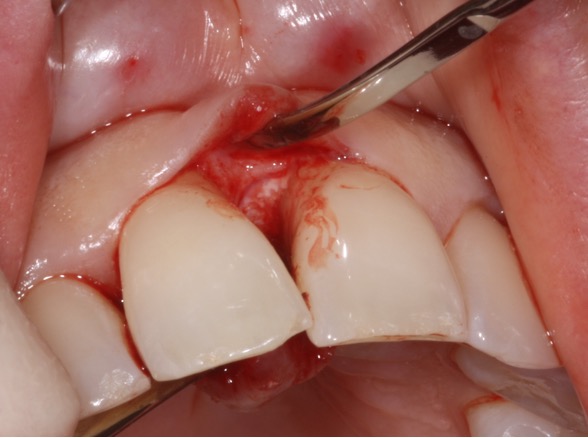

Recession surgery – connective tissue graft

A connective tissue graft is another way to cover recession. This takes a sub-layer of tissue from the palate. The advantage of this is more comfortable healing from the palate and a better colour match to the grafted area.